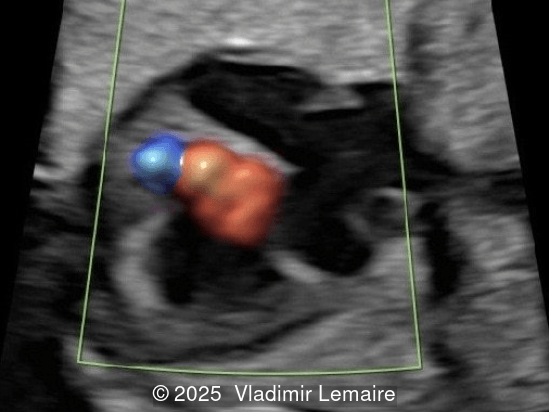

We present a case of isolated tricuspid atresia type 1 with persistent left superior vena cava. No other extracardiac anomalies were found. Our diagnosis was confirmed after birth.

In the images below, the abbreviations are as follows: RA: right atrium; RV: right ventricle; LV: left ventricle; MV: mitral valve; LA: left atrium; FO: foramen ovale; SVC: superior vena cava; LSVC: left superior vena cava; PV: pulmonary veins; PA: pulmonary artery; MPA: main pulmonary artery; RPA: right pulmonary artery; AO: aorta; dAO: descending aorta; aAO: ascending aorta; DA: ductus arteriosus; T: trachea; * marks the ventricular septal defect.

Color Doppler confirms the diagnosis on grayscale ultrasound, as it demonstrates the lack of blood flow across the tricuspid valve and a patent mitral valve. Due to increased blood flow across the mitral valve, aliasing is typically noted on color Doppler. Mitral valve regurgitation has been associated with a poor outcome. The right ventricular cavity is filled in late diastole from the left ventricle, through the ventricular septal defect. Left-to-right shunting across the ventricular septal defect can be seen on color Doppler. Color Doppler is helpful in the evaluation of flow across the great arteries. Flow across the pulmonary artery is generally antegrade. Pulmonary stenosis should be suspected when the vessel is diminutive in size rather than the demonstration of turbulent flow on color Doppler, which is typically absent in these cases.